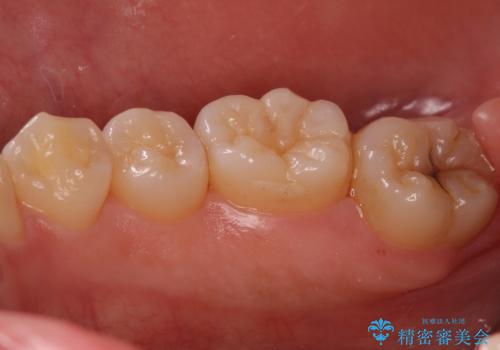

奥歯の深い黒ずみ セラミックインレーでの治療

変色しない材料をご希望されたためセラミックインレーでの治療となりました。

樹脂は変色していきますがセラミックは変色しない材料であるため、長く使いたい方にお勧めです。

- 右下7 セラミックインレー 77,000円費用は治療当時の料金となります